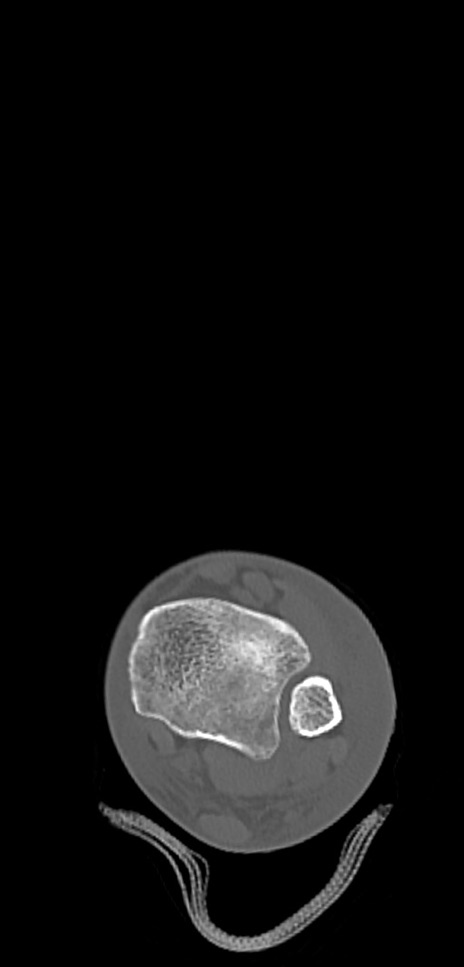

症例37 左足関節CT(横断像)

左足関節CT